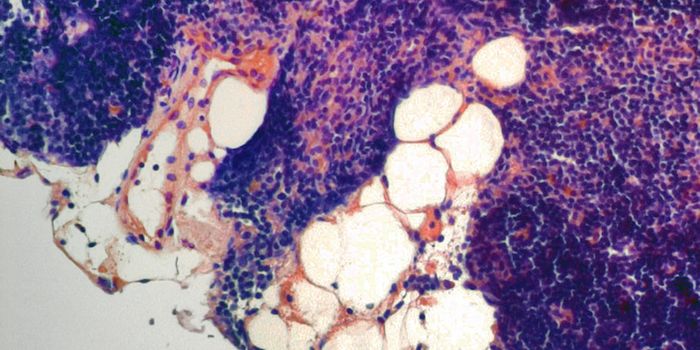

APR 24, 2015Cell & Molecular BiologyResearchers from the Universitat Autònoma de Barcelona (UAB) Department of Cellular Biology, Physiology, and Immunology, ...